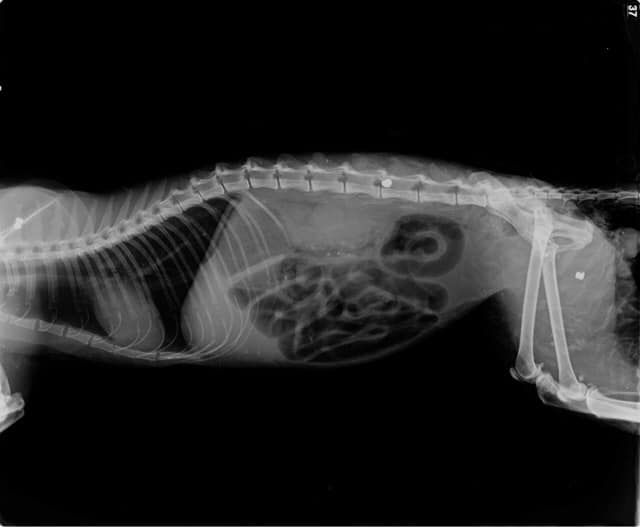

Ο γάτος μεταφέρθηκε άμεσα για πρώτες βοήθειες. Δυστυχώς στο κτηνιατρείο διαπιστώθηκε ότι ήταν πυροβολημένος πολλές φορές με αεροβόλο. Μετά τη λήψη ακτινογραφιών εντοπίστηκαν τρεις σφαίρες στο σώμα του, μια εκ των οποίων στη σπονδυλική στήλη.